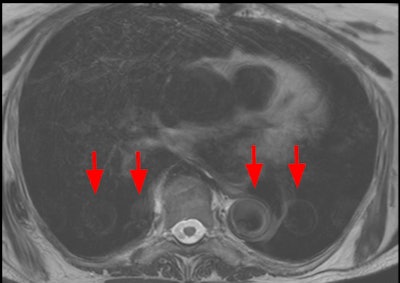

Dielectric artifact. Axial echo gradient fat-saturated T1-weighted slice of the abdomen acquired on a 3-tesla device, showing multiple blurred areas of signal loss (arrows) at distance of the receiving coil, in a patient with abundant ascites. The strategy in this case would be first to apply parallel radiofrequency transmission technique, and if insufficient, to rescan the patient on a 1.5-tesla scanner."Pregnant patients should always be explored at 1.5T," the authors pointed out. "Ascites can be handled by switching to a lower magnetic field device or drained before the exam. Parallel radiofrequency (RF) transmission or any other technology improving RF emission homogeneity will reduce dielectric effects (e.g., Philips' MultiTransmit, Siemens' TimTx, GE's MultiDrive, Canon's Multiphase Transmit).